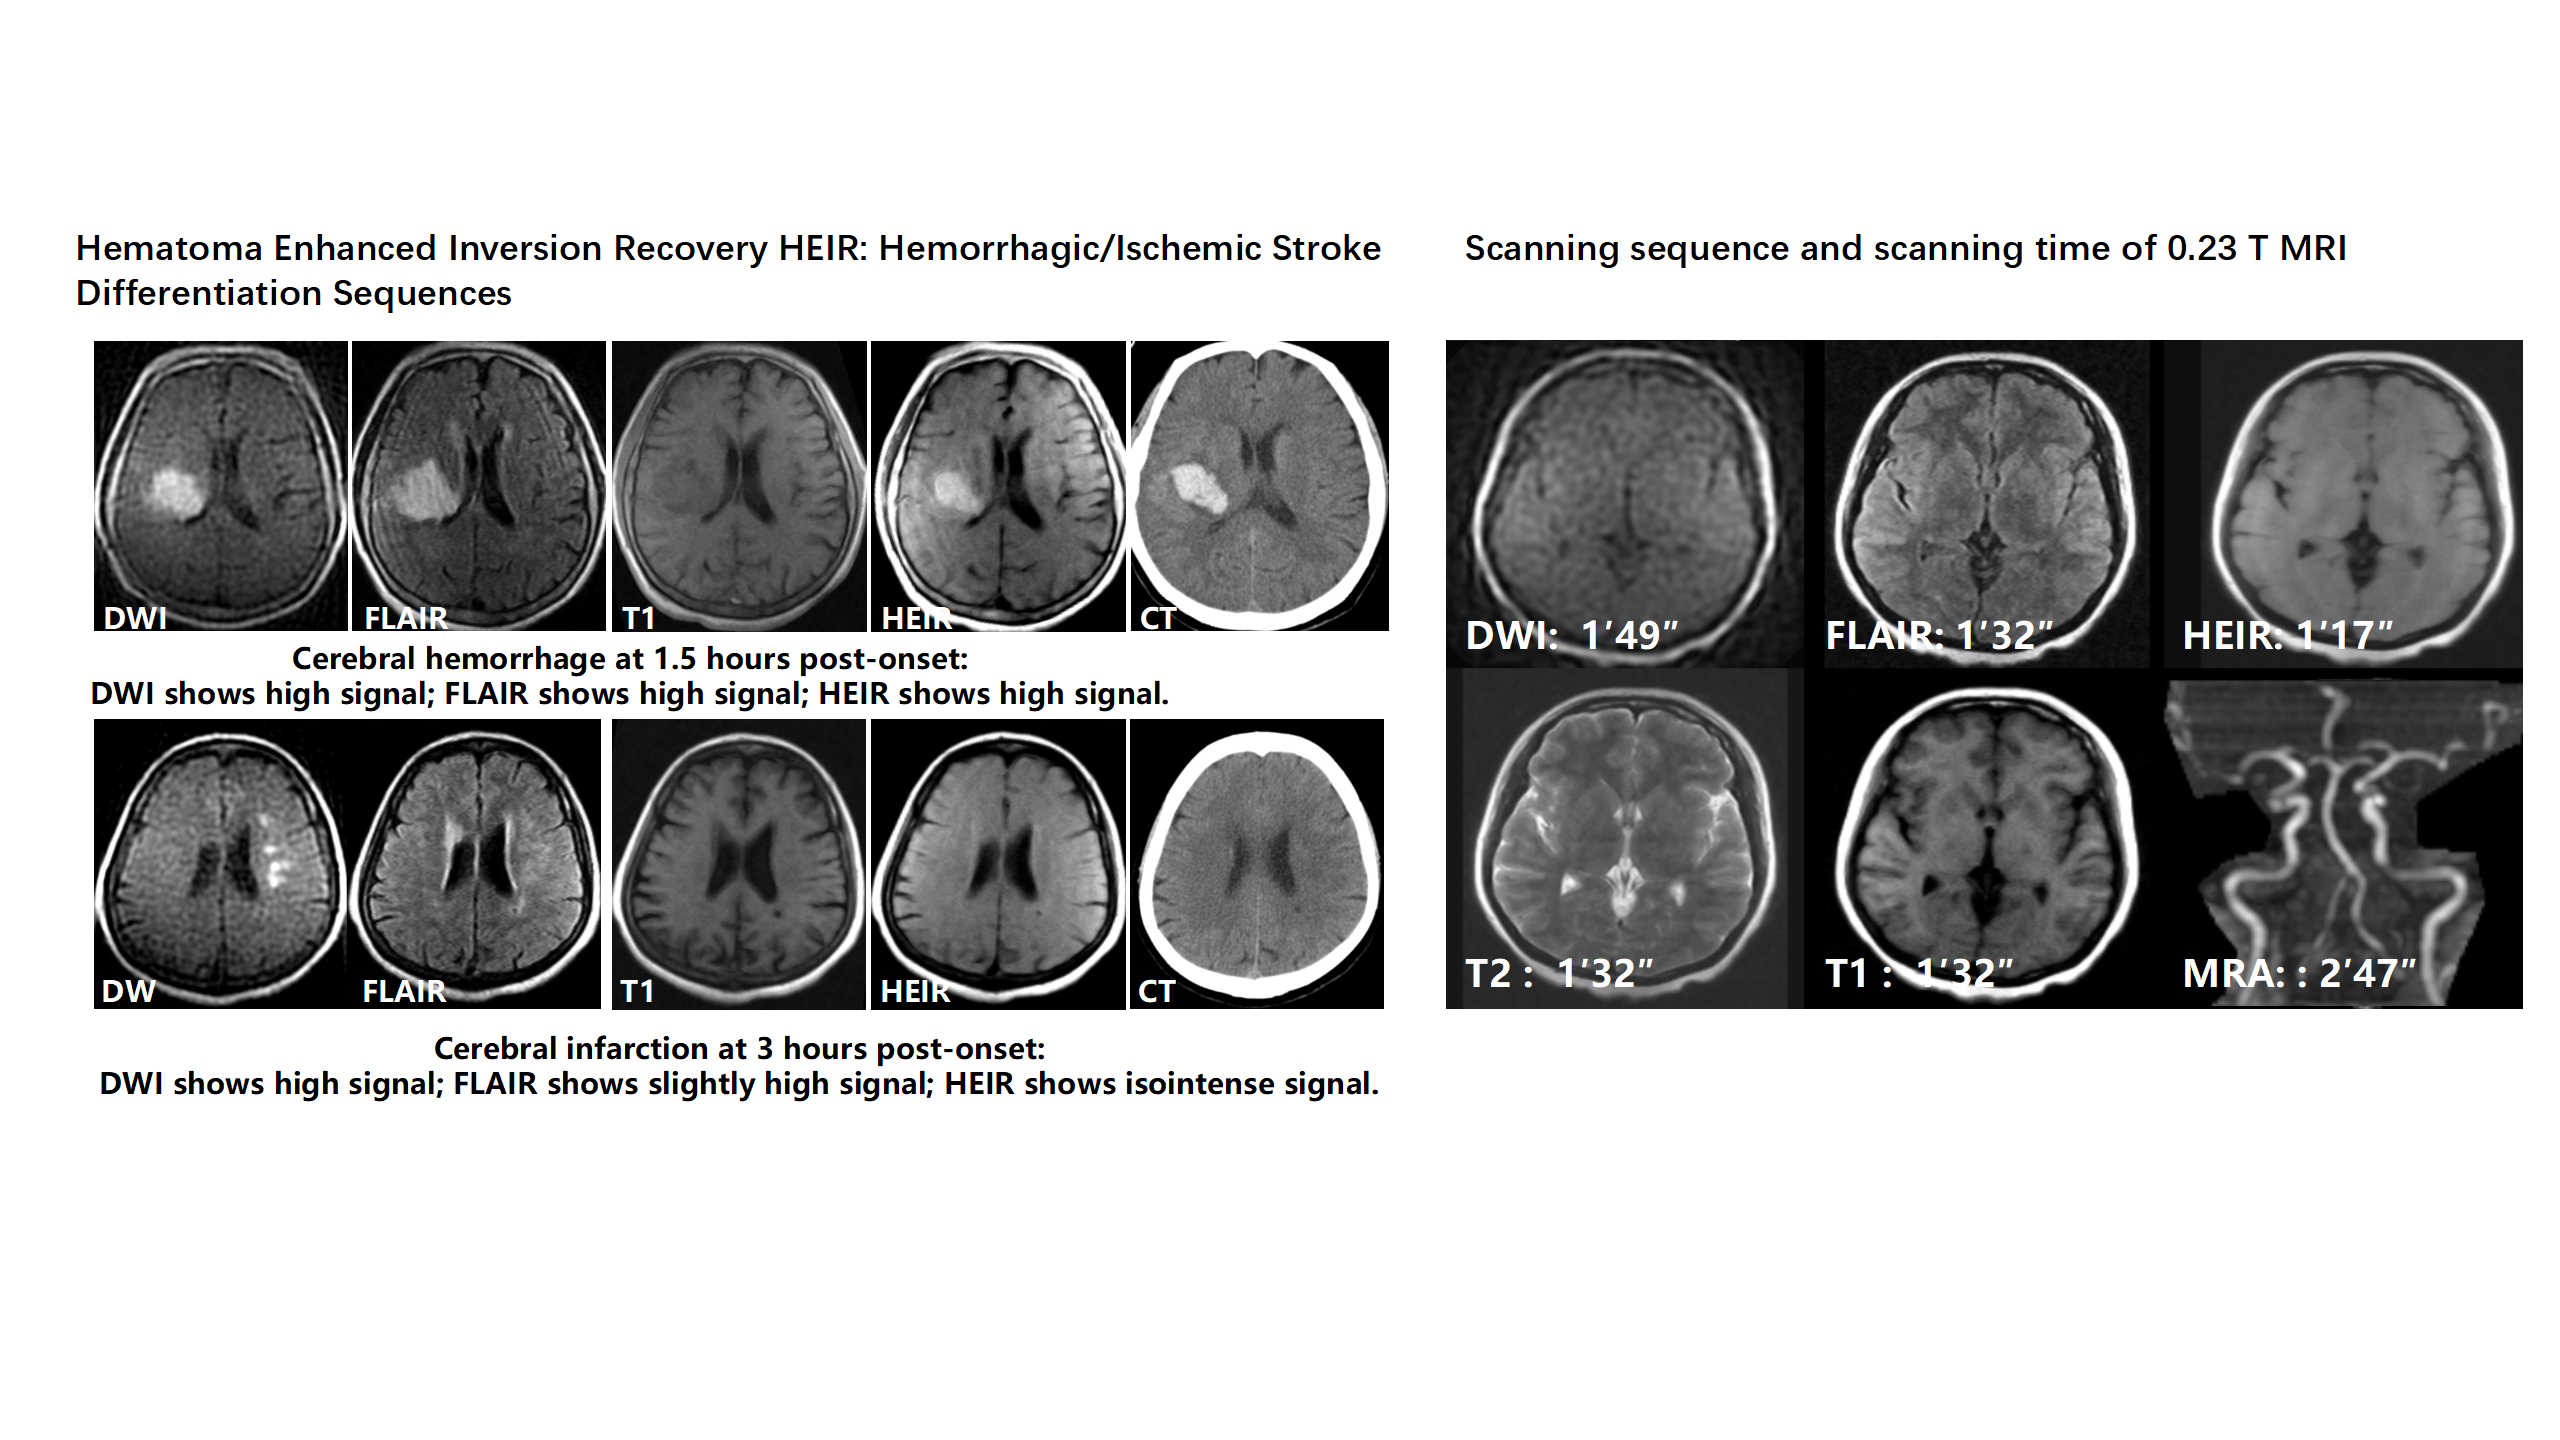

Abstract Body: Background—Intravenous thrombolysis(IVT)is an approved therapy for patients with acute ischemic stroke (AIS). In-hospital delay is one major concern prohibiting patients from receiving IVT. Emergency Stroke Unit (ESU), a new concept of stroke unit, was highly organized and managed in a centralized space at the Accident and Emergency Department and involved clinical evaluation, imaging assessment, and treatments. ESU was equipped with a 0.23-T mobile, low-field MR imaging (LF-MRI) scanner, enabling for distinguishment between acute phase cerebral hemorrhage and cerebral infarction (≤4.5 h) within 1 min and 17 seconds instead of routine CT, using the HEIR (Hematoma Enhanced Inversion Recovery) sequence we previously designed.